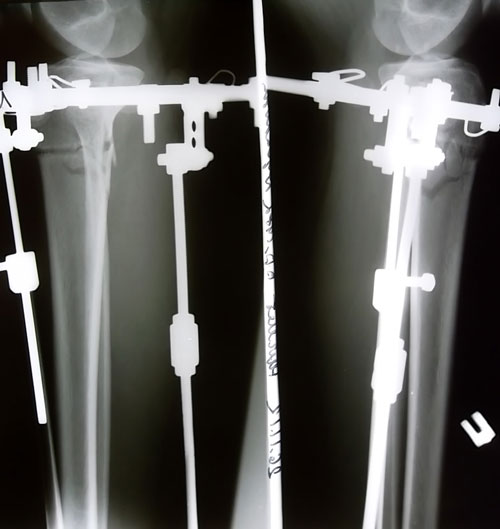

Ножки на сегодня.

Вложения

image_1.jpg

image_2.jpg